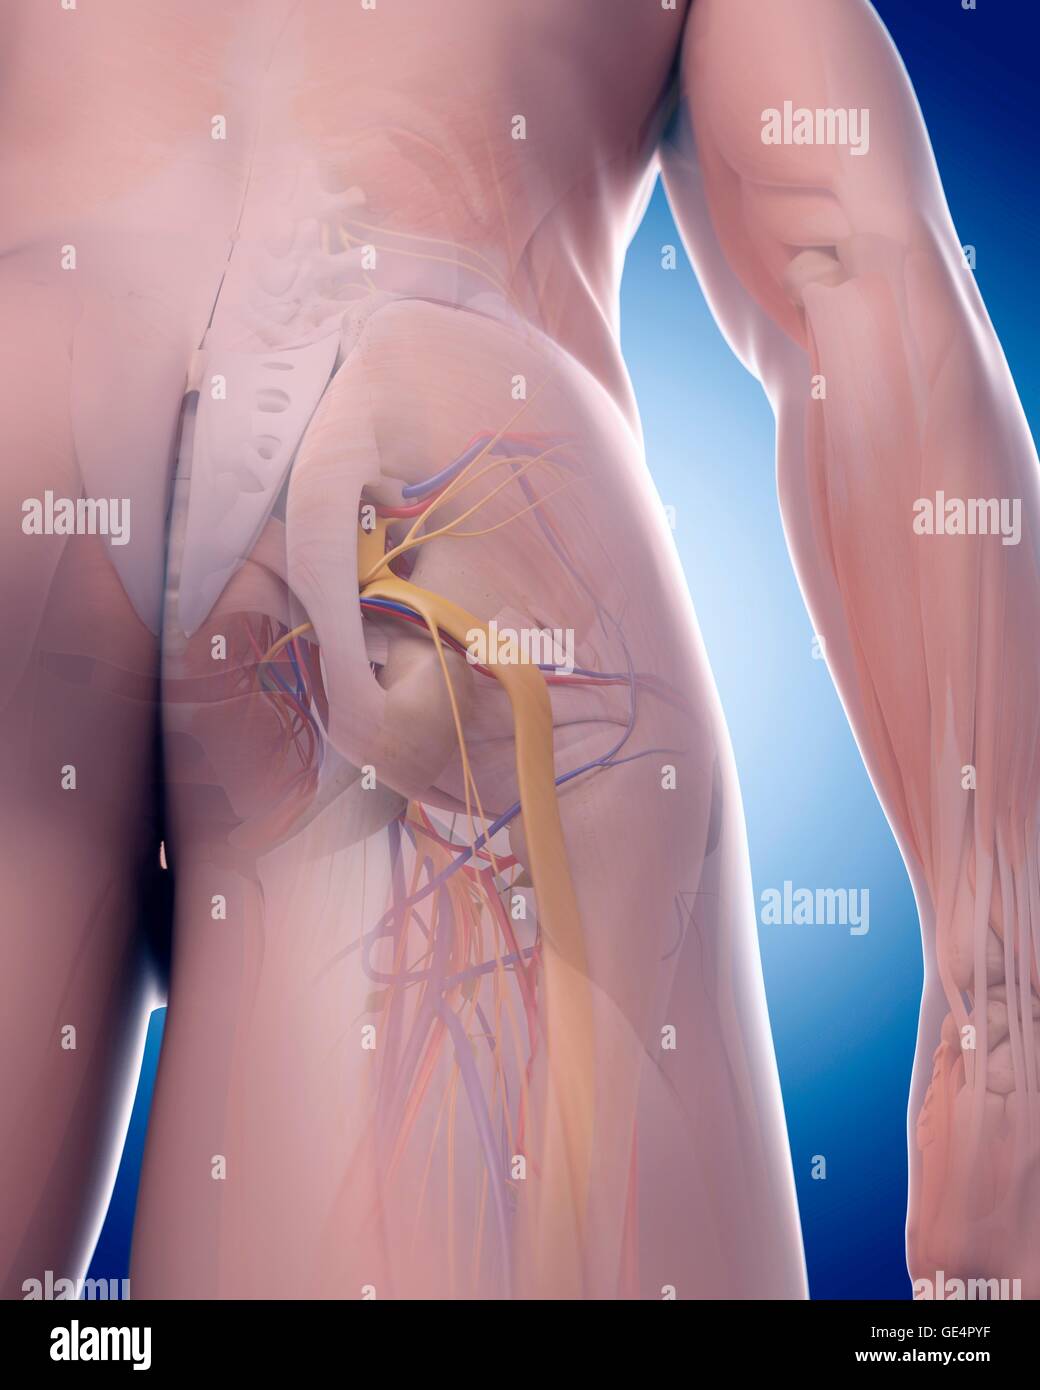

Nerf sciatique, l'illustration. Banque D'Imageshttps://www.alamyimages.fr/image-license-details/?v=1https://www.alamyimages.fr/photo-image-nerf-sciatique-l-illustration-111973219.html

Nerf sciatique, l'illustration. Banque D'Imageshttps://www.alamyimages.fr/image-license-details/?v=1https://www.alamyimages.fr/photo-image-nerf-sciatique-l-illustration-111973219.htmlRFGE4PYF–Nerf sciatique, l'illustration.